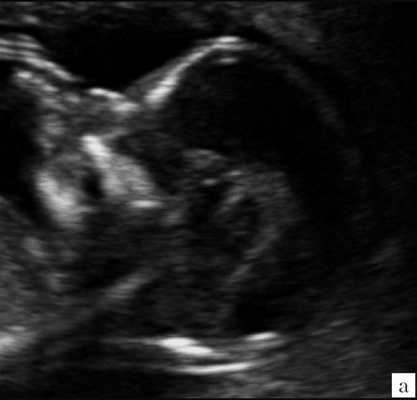

Особенностями визуализации этих структур является их гипо/анэхогенность. Так, при сроках 11-14 недель беременности таламус, ствол мозга, средний мозг выглядят практически анэхогенными. Итак, нормальная ультразвуковая анатомия этих структур головного мозга плода имеет следующие особенности: ствол и IV желудочек выглядят как анэхогенные продолговатые структуры, имеющие непосредственную близость (как бы выходящие) из диэнцефалона и среднего мозга. Все выше перечисленные анатомические структуры могут быть измерены и должно быть оценено их взаиморасположение (рис. 2, а).

а) На эхограмме:

1 - ствол мозга;

2 - интракраниальное пространство, или IV желудочек;

3 - большая цистерна головного мозга;

4 - воротниковое пространство.